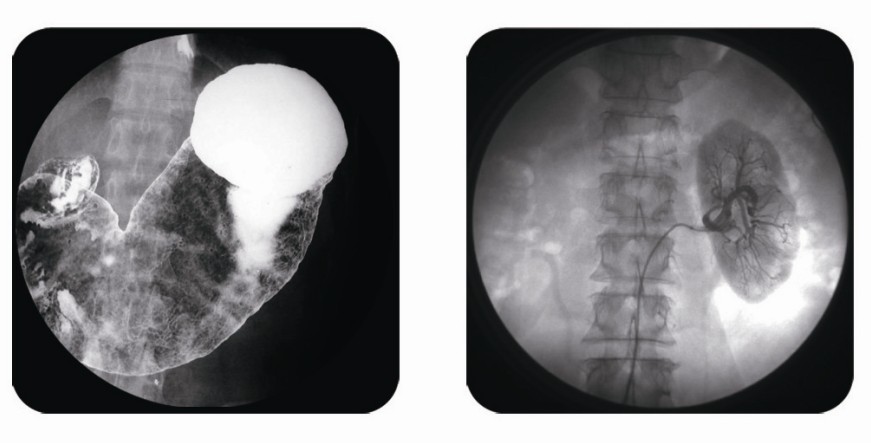

傳統(tǒng)胃腸造影檢查,病變顯示率低,輻射劑量大。普朗醫(yī)療器械公司生產(chǎn)的幾款多功能腸胃造影x光機(jī),更能滿足不同等級不同規(guī)模的大小醫(yī)院選擇,從臨床及科研都很好。尤其最新的PLD8800多功能腸胃造影x光機(jī)用途更為廣泛。多功能腸胃造影x光機(jī)是目前各大醫(yī)院最普及的且用途最廣的一種X光機(jī)。普朗醫(yī)療的胃腸機(jī)功能多,簡便易用,能保證圖像質(zhì)量,該機(jī)采用高制式電視系統(tǒng),優(yōu)秀的數(shù)字化系統(tǒng)能使多功能腸胃造影x光機(jī)的性能得到提高,應(yīng)用范圍獲得極大的拓寬。

1、一般應(yīng)用:數(shù)字透視,動態(tài)及多方位觀察器官病變,圖像更清晰,并可保留末幀圖像;既可使用暗盒完成常規(guī)X線拍片,這是其最大的優(yōu)勢,拍片質(zhì)量大大提高。

2、特殊檢查的應(yīng)用:如“T”管造影、消化道鋇餐、靜脈腎盂造影、子宮輸卵管碘油造影等,在實(shí)時監(jiān)視的同時隨時采集,抓住關(guān)鍵圖像,并可連續(xù)采集,電影回放整個過程。

3、介入方面的應(yīng)用:能很好開展全身各部位的血管造影、藥物灌注、栓塞治療及經(jīng)皮穿刺活檢引流,主要應(yīng)用于血管造影診斷及腫瘤的治療,不明原因腫塊的性質(zhì)確定。